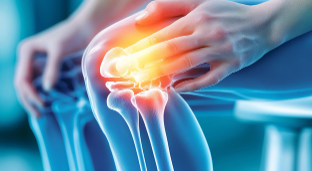

관절은 단순한 움직임의 연결점이 아니라, 우리 몸의 활동성과 삶의 질을 좌우하는 핵심 구조입니다. 그러나 잘못된 생활습관과 무리한 활동은 관절에 부담을 주어 퇴행성 질환을 촉진할 수 있습니다. 이번 글에서는 의학적 근거를 바탕으로 관절을 효과적으로 보호하는 운동 원리와 관절 건강에 도움이 되는 식품을 상세히 소개합니다.

관절 보호 운동의 과학적 원리

넷째, 스트레칭과 가동성 훈련을 통해 관절의 운동 범위를 유지해야 합니다. 움직임이 제한되면 관절 주변 조직이 굳어 통증과 손상을 유발할 수 있습니다.

관절 운동은 ‘따뜻하게 준비 → 천천히 움직이기 → 마무리 스트레칭’ 순으로 진행해야 효과적입니다.